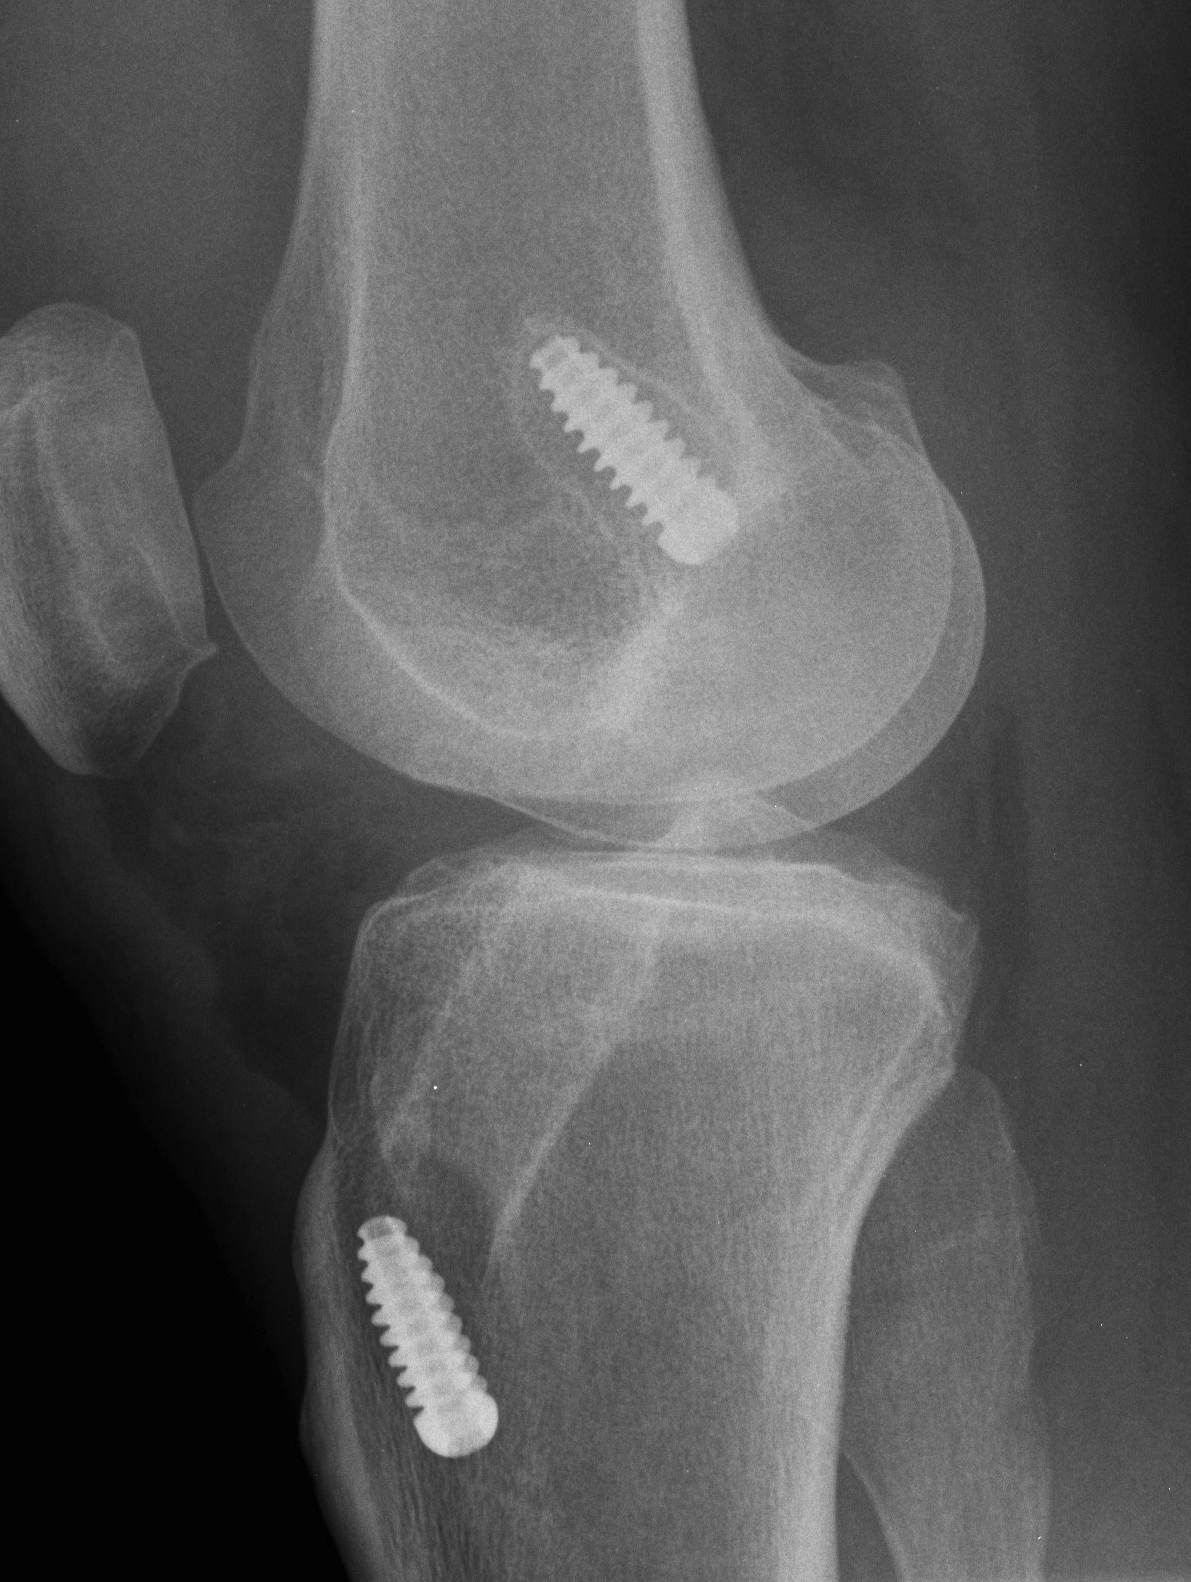

CT

Assess for tunnel lysis

2.  Correct tunnel position, increased size secondary to lysis

Tibial and femoral tunnel Lysis

Staged bone grafting of tunnels

- use bone cores from iliac crest

- premade synthetic bone graft plugs

- wait for union / 3 - 6 months

- ACL revision

BTPB / Achilles allograft with larger bone block